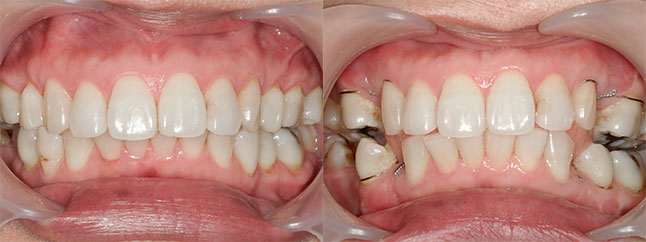

大阪府 19歳 男性

執刀医 辻和志

【治療内容】上下セットバック…上のアゴと下のアゴの両方が前に出ていた為、上下のアゴの骨を切って後ろに下げました。

【費用】上下セットバック 2,307,800円(税込)

【リスク】全身麻酔で行うため全身の健康状態が悪い方は行うことができません。また、手術当日は安静にしていただく必要があります。